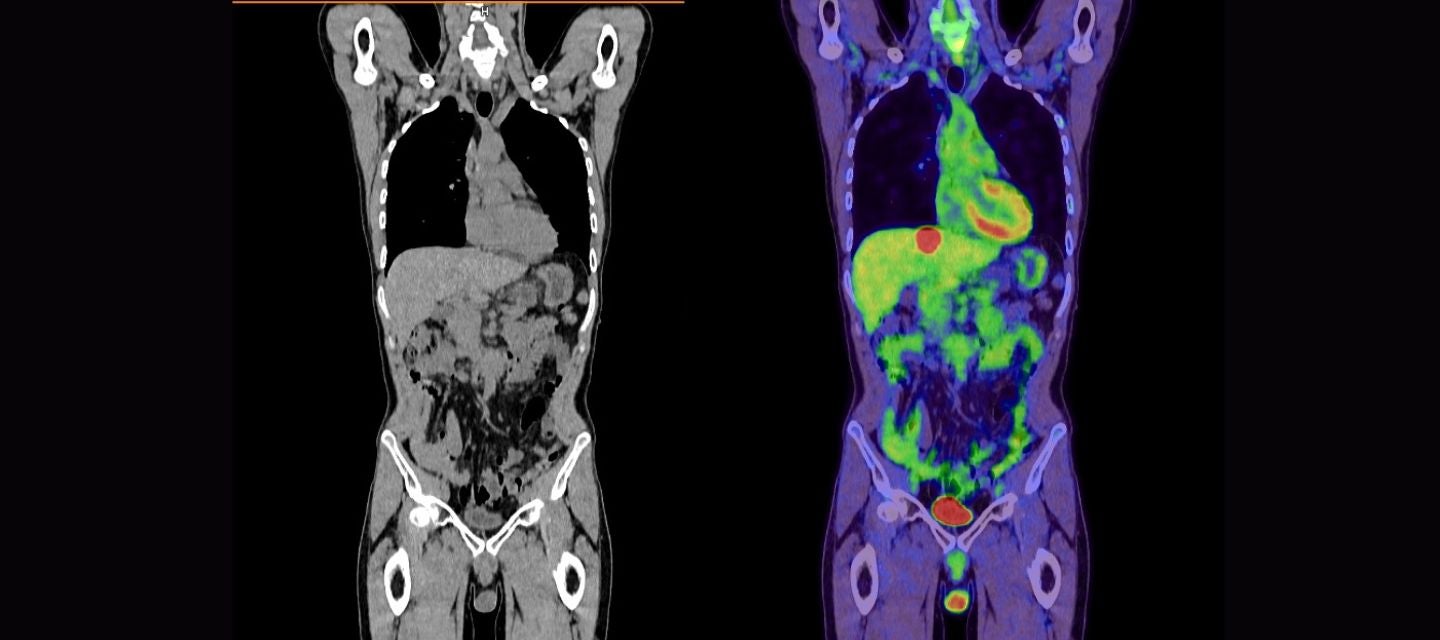

There are two parts to a PET-CT scan, both are performed on the same scanner at the same time.

Positron emission tomography, known as PET, is a nuclear medicine imaging test in which a small amount of liquid radioactive material is injected into your body to provide functional information about the body. The radioactive substance most used in PET scanning is a simple sugar (like glucose) called FDG, which stands for “fluorodeoxyglucose”. It is injected into your bloodstream and accumulates in your body where it gives off energy in the form of gamma rays. These are detected by the PET scanner and a computer converts the signals into detailed pictures or images showing how tissue and organs are working. If you are having an FDG PET, your sugar metabolism (how sugar is used by your body) is imaged. More information on the type of radioactive tracers is provided below.

CT (Computed tomography) imaging uses x-ray equipment to create detailed images of slices of the anatomy/structures inside of your body.

Both PET and CT scan information is displayed in the form of images and then combined or fused to form the PET-CT.

The PET-CT combination allows any abnormality on the PET scan to be precisely located within the body, allowing for accurate diagnosis of a variety of conditions, including many types of cancers, heart and other diseases.